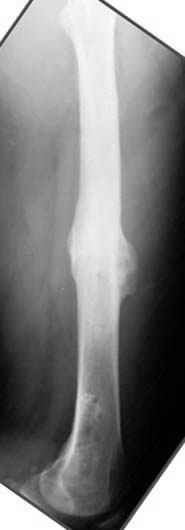

пластическая модель; и коррекция бедра аппаратом Илизарова.

Имею другие снимки тоже, получится как отчет о моей работе.

С уважением Джолдас